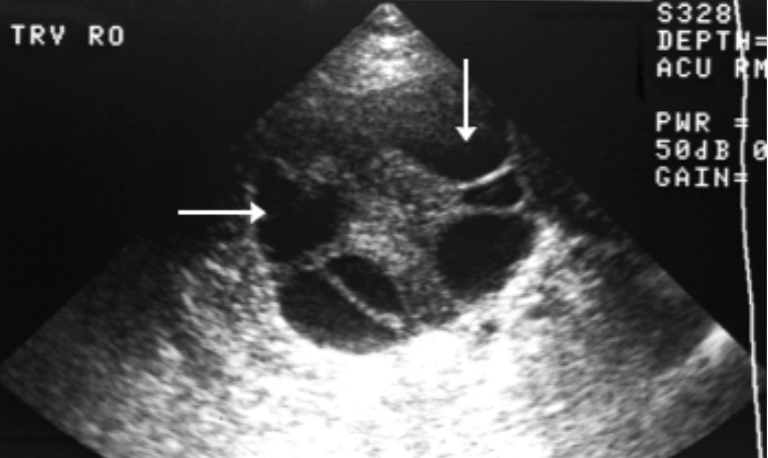

Coexistent Molar & Fetus

Rare

results from hydatidiform degeneration of twins

More likely w/ 2 placentas, coexisting fetus alive w/ normal placenta